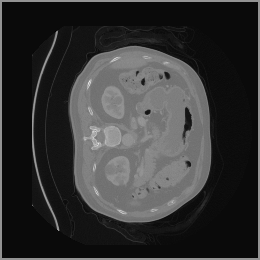

The motivation for this work arises from the need to address these limitations in the synthesis of 3D medical images. Current techniques do not produce high-resolution 3D images that preserve spatial coherence and capture the full complexity of medical data, as shown in Figure 2, 5. The development of advanced 3D generative models tailored specifically for medical imaging could not only improve the quality of synthetic medical images but also help alleviate data scarcity, enhance privacy protection, reduce computational requirement and ultimately advance the use of deep learning in healthcare applications.

To demonstrate the advantages of 3D semantic image synthesis over 2D semantic semantic image synthesis, we conducted a detailed comparison with the SegGuidedDiff [26] model. SegGuidedDiff generates medical images based on 2D semantic maps, producing individual 2D slices that are later stacked to form a 3D image. However, this approach has limitations in capturing spatial continuity and coherence across slices, which is critical for representing the spatial structure of 3D medical images. As a result, inconsistencies often arise between different slices, particularly in preserving anatomical structures across the coronal and sagittal planes. The generated images exhibit varying levels of denoising, resulting in differences in brightness and sharpness across the images. This inconsistency in denoising can lead to noticeable variations in visual quality, where some regions appear clearer and others less distinct.

As shown in Figure 5, the generated slices exhibit high consistency across adjacent slices. The anatomical structures and semantic patterns are smoothly and coherently preserved between slices, indicating that our model is capable of generating 3D-consistent synthetic images rather than isolated 2D slices.

Figure 8 further supports these findings: the images generated by Med-LSDM preserve spatial coherence across coronal and sagittal planes, whereas those from SegGuidedDiff show noticeable inconsistencies. These artifacts likely result from the 2D nature of SegGuidedDiff, which fails to account for 3D spatial relationships. In contrast, our model’s volumetric diffusion framework inherently preserves anatomical consistency, highlighting its advanta in synthesizing high-fidelity 3D medical images.